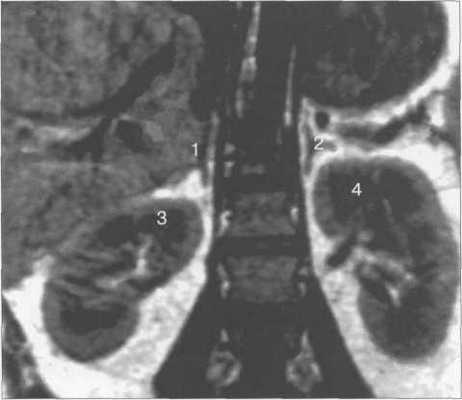

Локализация, размеры и форма надпочечников в МРТ-изображении не отличаются от указанных параметров при КТ. Исследование в корональной плоскости позволяет более четко оценить месторасположение железы, ее высоту (рис. 12.6).

Рис. 12.6. МРТ надпочечников. Т1-ВИ, корональная плоскость.

1 — правый надпочечник; 2 — левый надпочечник; 3 — правая почка; 4 — левая почка.